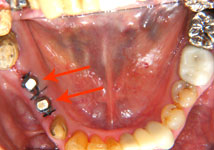

| インプラントを植立したところ |

植立して1か月後 |